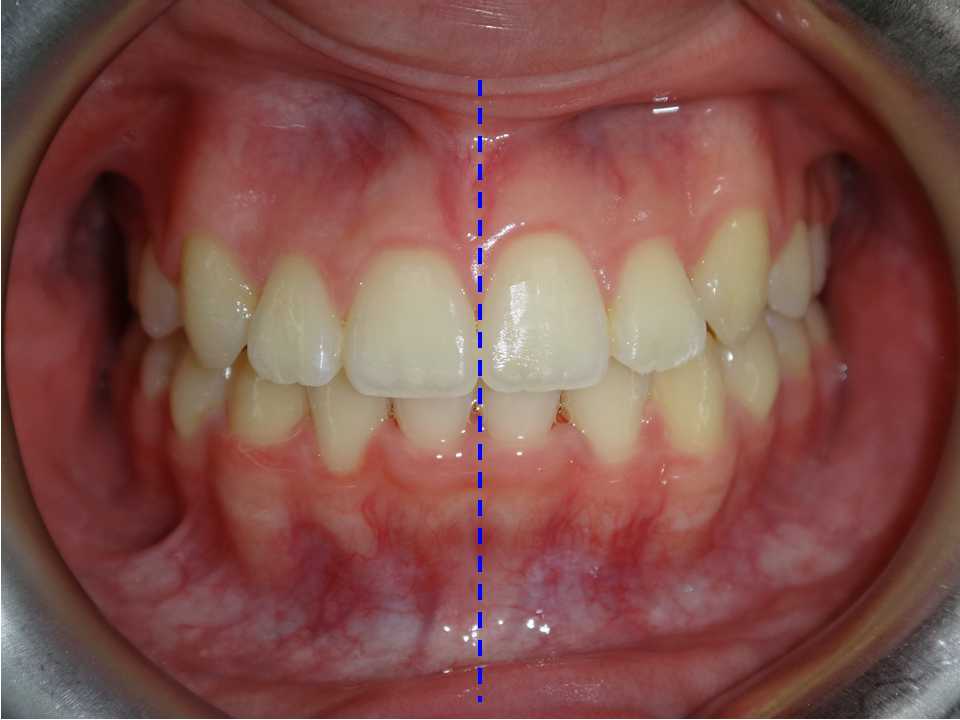

自鎖式矯正器不拔牙矯正 首頁 案例分享 齒顎矯正 自鎖式矯正器不拔牙矯正 中線歪斜致使下巴偏右,經矯正後改正 年紀:17歲 女性 時間:26個月 矯正前 矯正後 聲明:本所療程皆由專業醫生評估後,依照個人口腔狀況進行治療。因每位患者個別狀況不同,術後狀況也不盡相同,需親來本所由醫生評估。